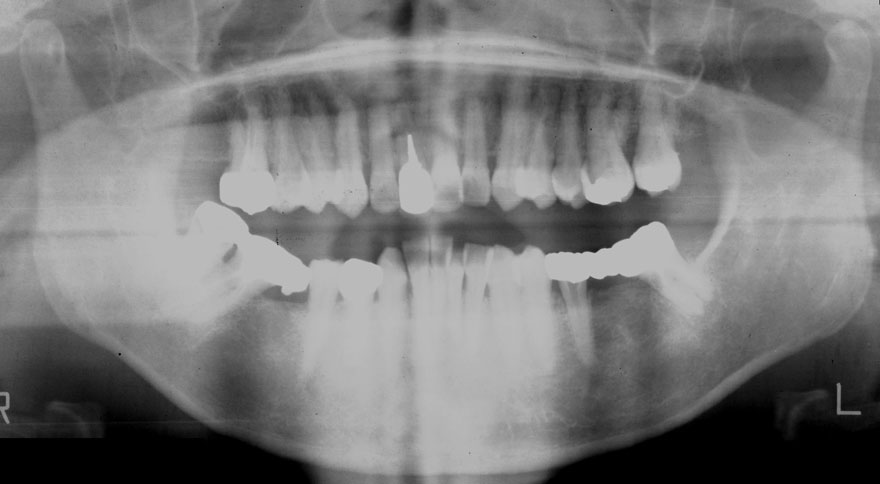

初診時 42歳 男性 平均歯槽骨喪失量:5.30mm

河田歯科医院

22年後 64歳

平均歯槽骨喪失量:5.554mm

22年間喪失量:-0.24mm

年間喪失速度:-0.01mm

(ケア頻度:1.07ヵ月ごと)